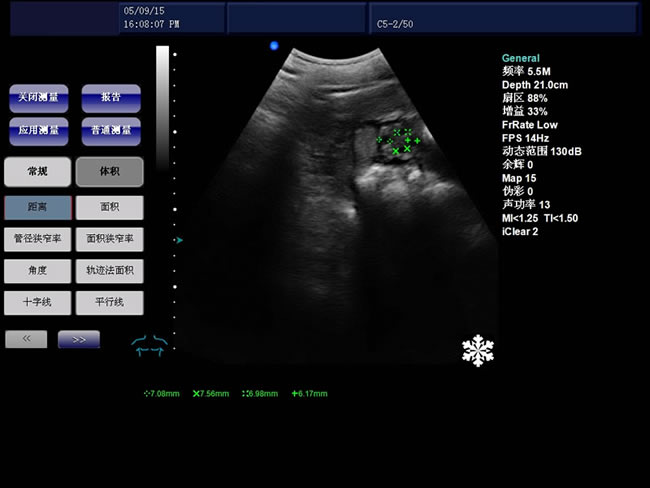

S8 彩色多普勒獸用超聲診斷儀

• S8彩色多普勒獸用超聲診斷儀是徐州市大為電子設備有限公司推出的一款全新的彩色超聲診斷儀器。

B模式基本測量:距離、角度、周長和面積(橢圓法、軌跡法)、體積、直方圖、斷面圖